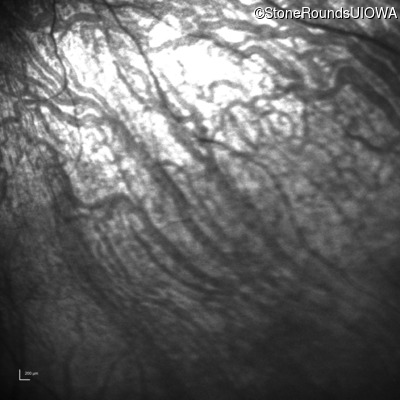

Infrared Fundus Photograph - Left -

No Light Perception

Exemplar

Expanded OCT Stack

×